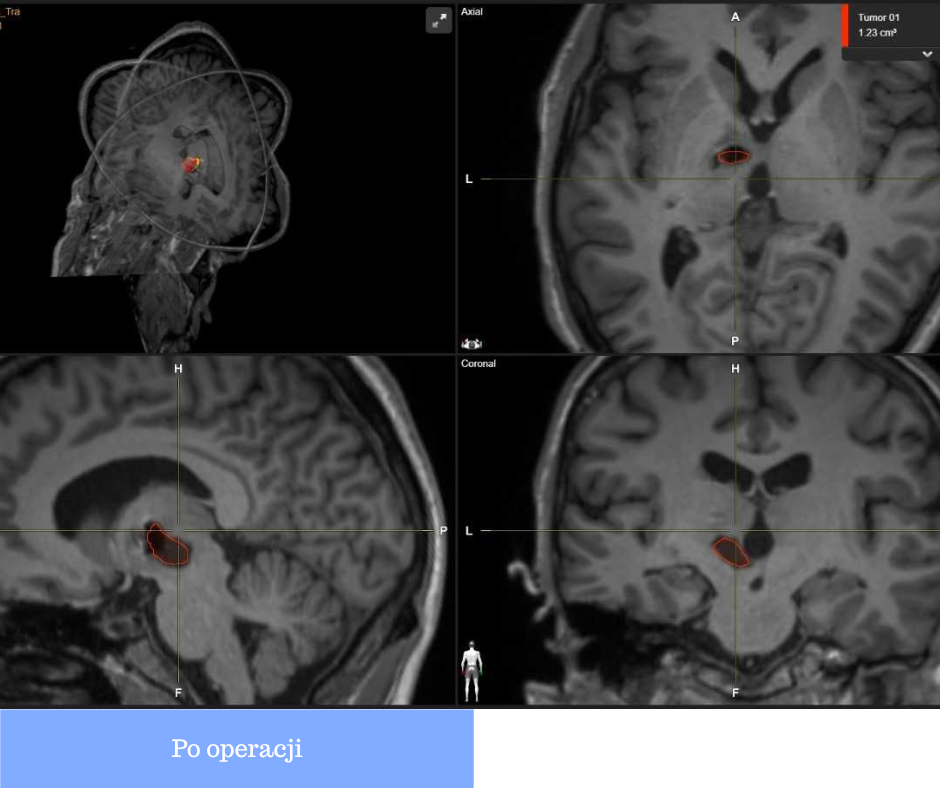

Z badań tomografii wiedzieliśmy, że jest to torbiel z płynem o gęstości wody. I faktycznie udało nam się zdrenować zmianę. Ściągnęliśmy 11 cm sześciennych płynu.

Operacja odbyła się w październiku 2025 r. Kiedy pan Adam się obudził, bliscy od razu wiedzieli, że zabieg się powiódł.

Pobrany w czasie operacji płyn przekazano do badania histopatologicznego. Pacjent będzie wymagał dalszego nadzoru aby w porę wykryć ewentualny nawrót zmiany.

Nowoczesność ratująca życie

Rzeczniczka USK w Białymstoku Katarzyna Malinowska-Olczyk podkreśla, że podczas zabiegu zastosowano neuronawigację – supernowoczesne urządzenie, które szpital zakupił dzięki realizacji projektu „Neurodoskonałość bez granic” (akronim Neuroexcellence) realizowanego w Programie PL-UA.

Przypadek pana Adama pokazuje, jak dużą różnicę w codziennej pracy lekarzy może zrobić odpowiednio dobrany, nowoczesny sprzęt. Dzięki projektowi specjaliści z USK w Białymstoku mają dziś możliwość stosowania rozwiązań, które pozwalają przeprowadzać zabiegi mniej inwazyjnie, bezpieczniejsze dla pacjentów.